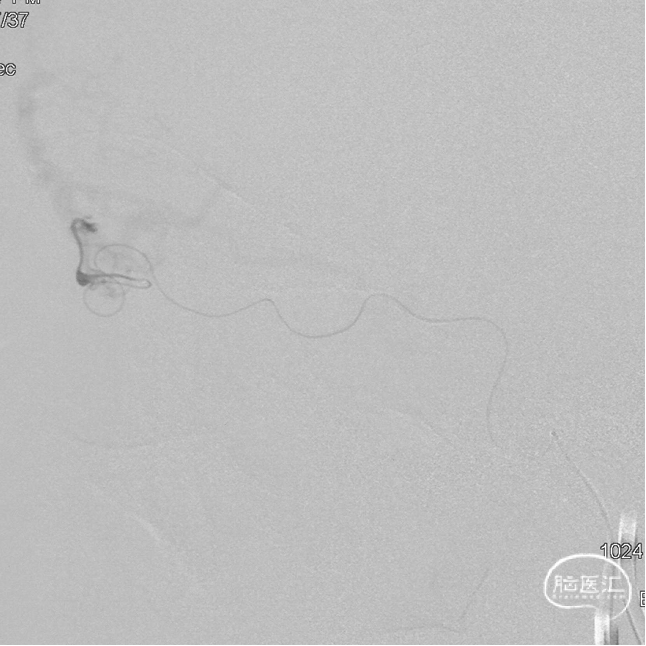

最终造影瘘口完全不显影。

双侧脉络膜染色正常。

Onyx胶铸型进一步显示了瘘的结构。AFA:镰前动脉;AEA:筛前动脉;PEA:筛后动脉;DV:引流静脉。